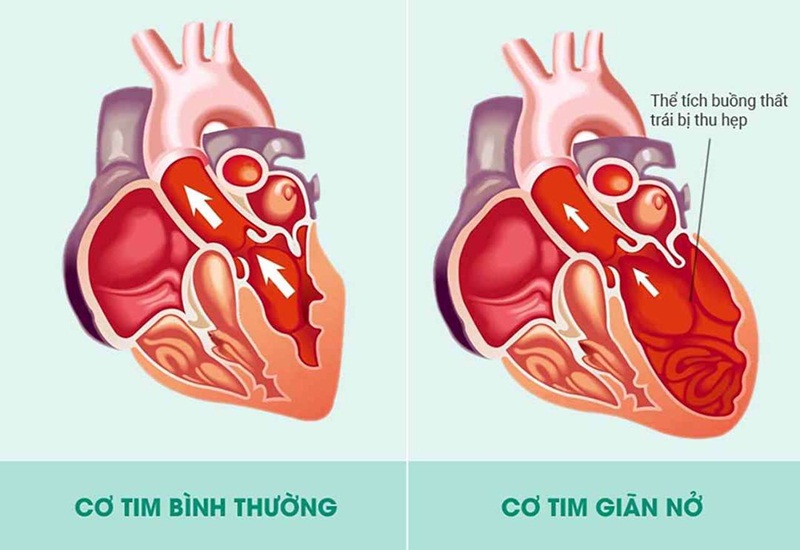

Cơ tim giãn hình thành cục máu đông gây đột quỵ nhồi máu não

Cơ tim giãn là căn bệnh nặng, có tiên lượng xấu và có tỷ lệ tử vong khá cao. Bệnh lý này nếu không được phát hiện và điều trị kịp thời sẽ gây các bệnh nghiêm trọng về tim mạch như: Hở van tim, suy tim, rối loạn tâm trương,… Thậm chí, có thể dẫn đến đột quỵ hoặc tử vong.